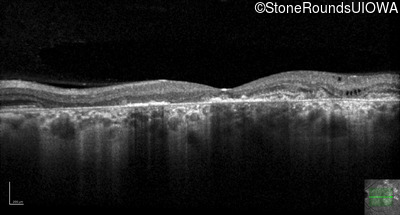

AR Stargardt Disease (IIA)

Age at visit: 56 years

This 56 year old man underwent surgery for strabismus in early childhood. He felt that his vision was good for most of his life, but about 5 years ago he first experienced difficulty following a golf ball in flight.

Diagnosis & molecular findings

Disease Gene Allele 1 variant(s) Allele 2 variant(s) Inheritance mode

AR Stargardt Disease ABCA4 Asn965Ser AAT>AGT Glu2131Lys GAA>AAA AR